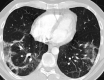

The potential mid-term and long-term consequences after severe acute respiratory syndrome coronavirus 2 (SARS-CoV-2) infections are as yet unknown. This is the first report of bronchoscopically verified organizing pneumonia as a complication of coronavirus disease 2019 (Covid19). It caused persisting dyspnea, impaired pulmonary function, and radiological abnormalities over 5 weeks after onset of symptoms. While organizing pneumonia frequently requires treatment with systemic corticosteroids, in this case it resolved spontaneously without treatment after 6 weeks. Healthcare professionals should consider organizing pneumonia in patients with persisting respiratory symptoms after Covid19.